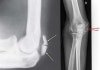

5. Patella cubiti

Patella cubiti is a very rare anomaly of the elbow, presenting as a sesamoid within the distal triceps brachii tendon.

Its exact aetiology is unknown with congenital, developmental and post-traumatic theories postulated.